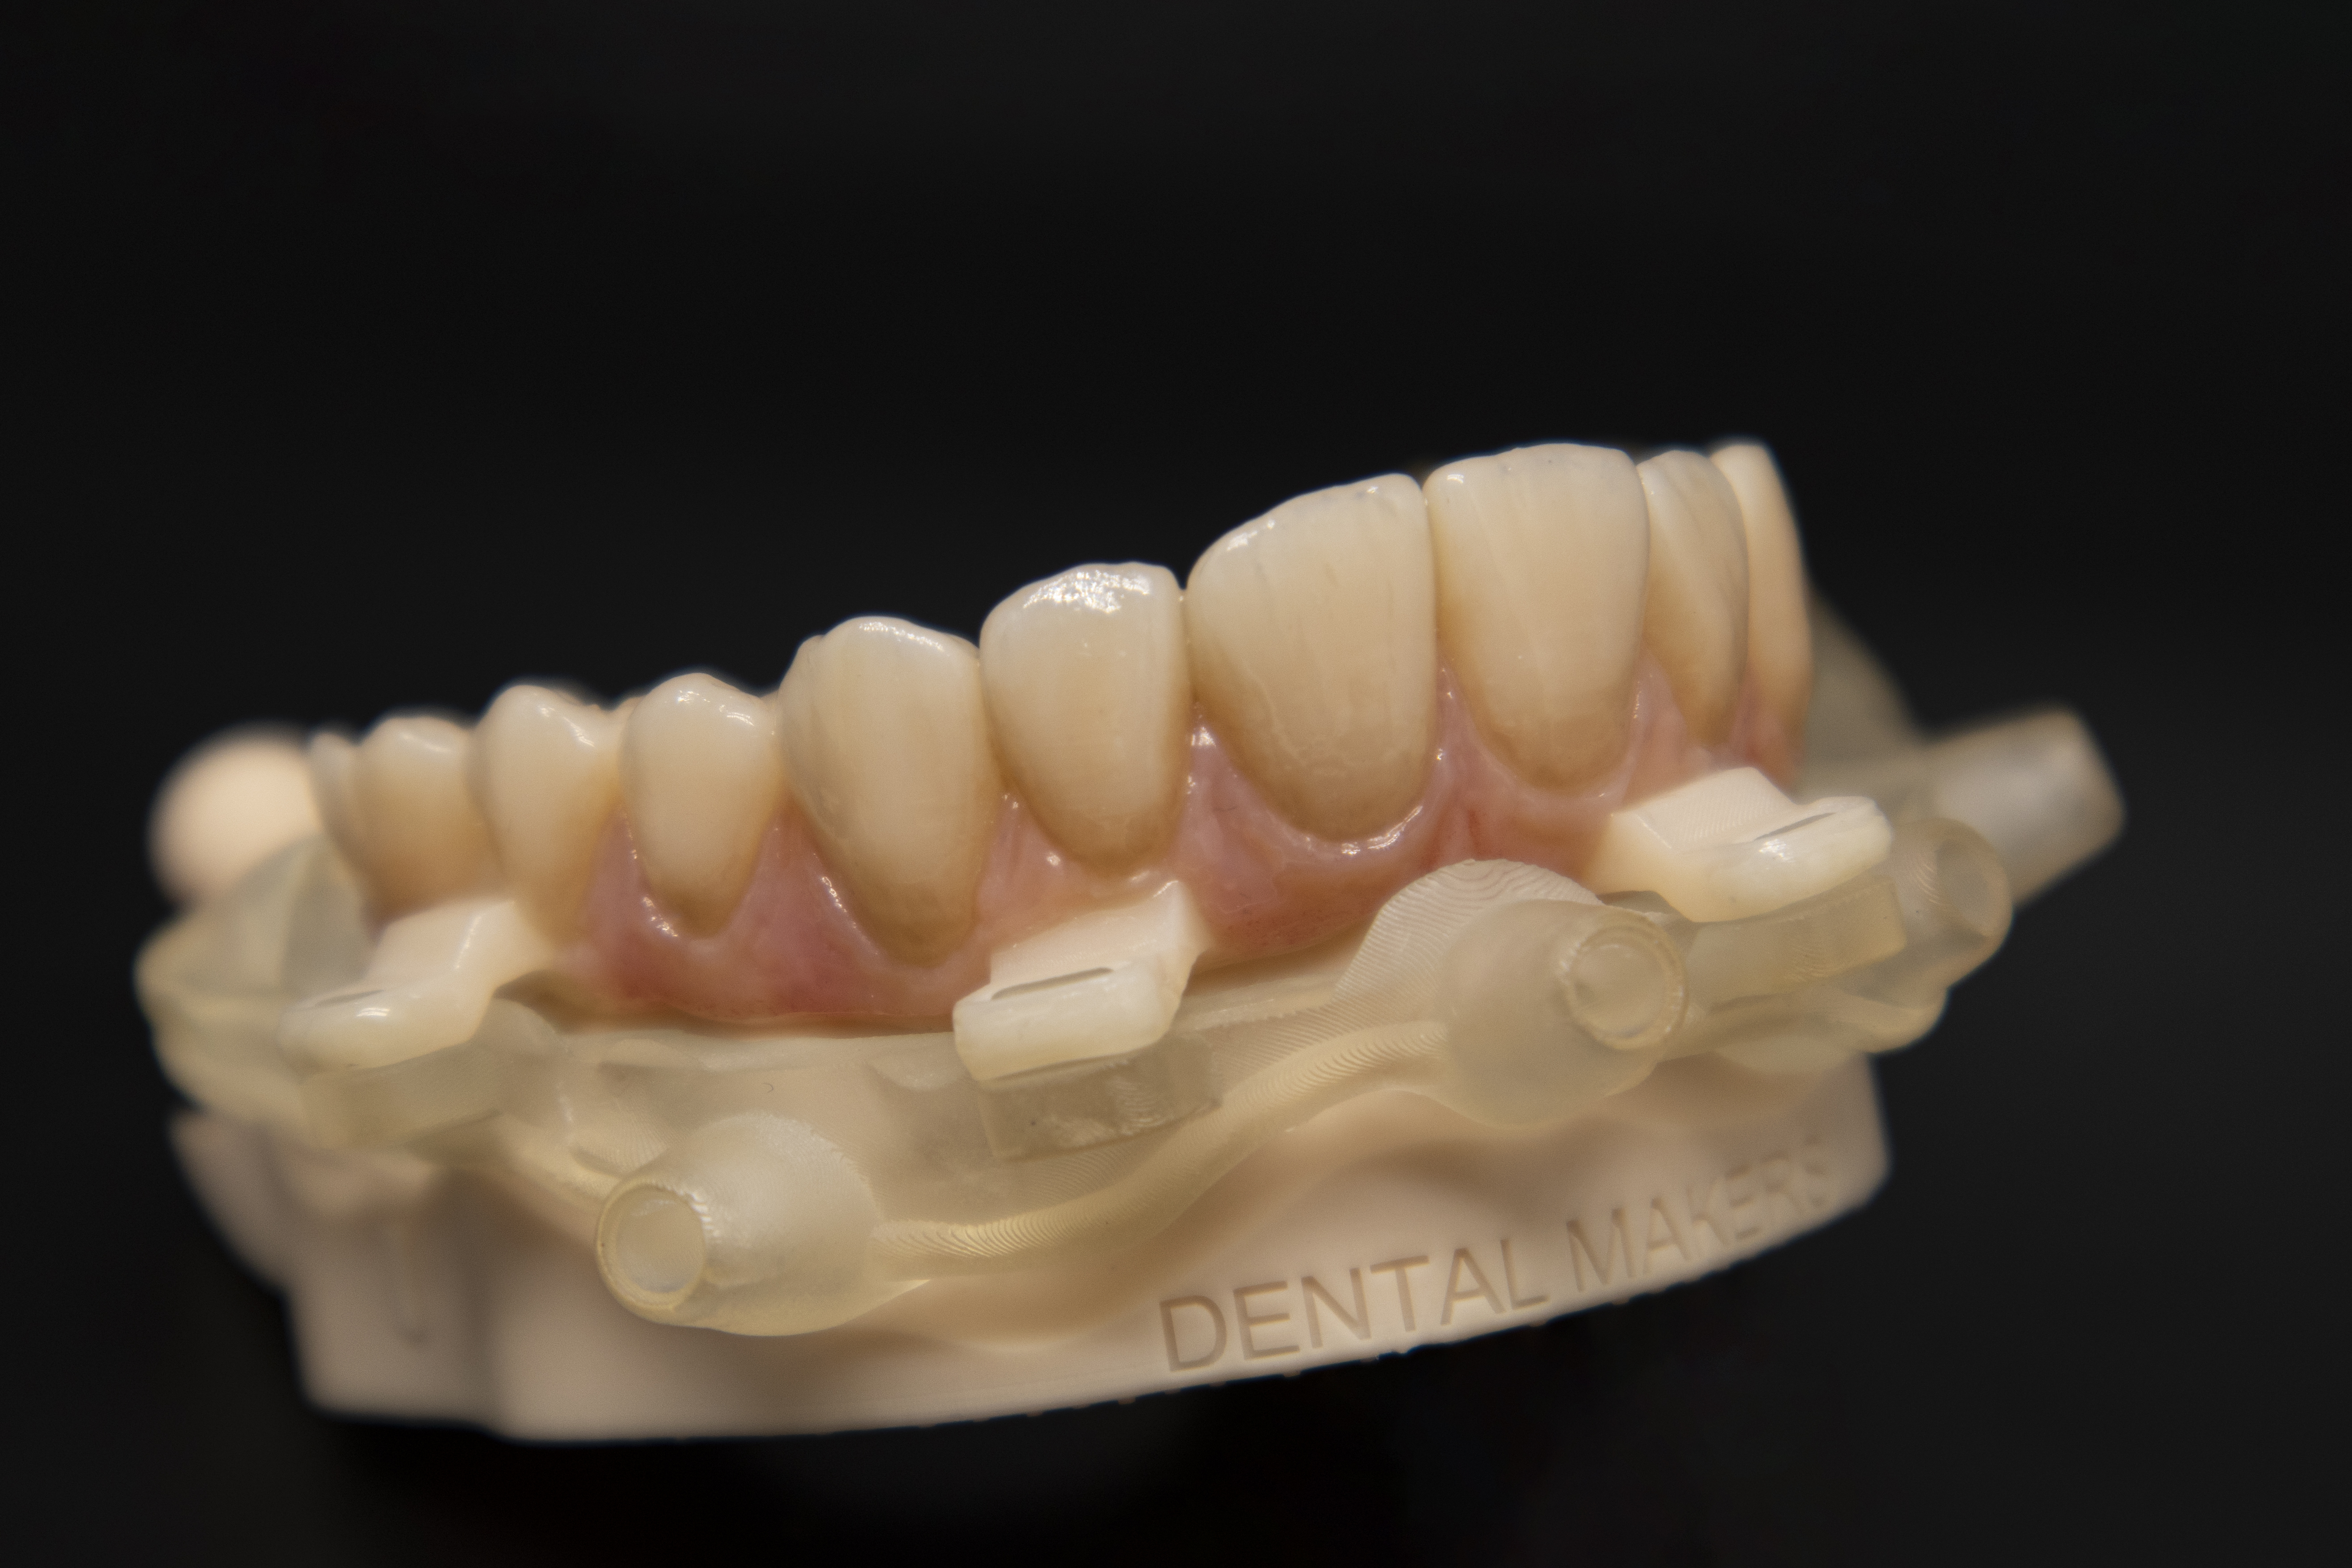

La decisione di utilizzare connessioni IPD MUA Multi Unit Non Engaging (IPD DentalGroup-Abutment Compatibili) ha arricchito ulteriormente il processo, offrendomi la flessibilità necessaria per adattare la protesi in modo che si integrasse perfettamente, non solo con l'aspetto fisico, ma anche con la vita del paziente. Questa scelta, benché tecnica, nasconde un profondo impegno verso il benessere del paziente, un principio che guida ogni nostra azione professionale (Fig. 3). Quando ho osservato la protesi completa per la prima volta, stampata con precisione e poi delicatamente ricoperta in composito, ho sentito un misto di orgoglio e umiltà. Questo non era solo il culmine di un trattamento odontoiatrico, ma la manifestazione fisica della mia passione e dedizione. Ogni dettaglio, dalla selezione dei materiali alla cura nella finitura, era un riflesso del mio viaggio personale nell'odontoiatria digitale (Fig. 4). Condividere questo risultato con il clinico e il paziente è stato un momento che ricorderò per sempre. Vedere la sua espressione trasformarsi, da timida speranza a gioia incontenibile, mi ha ricordato perché ho scelto questa carriera. L'odontoiatria digitale e la stampa 3D non sono solo avanzamenti tecnologici; sono strumenti che, nelle mani giuste, possono trasformare vite. Guardando al futuro, sono elettrizzato dalle infinite possibilità che la stampa 3D porta all'odontoiatria. Ogni giorno nel mio laboratorio è un'opportunità per esplorare, innovare e, soprattutto, fare la differenza nella vita delle persone. La mia storia con l'odontoiatria digitale è appena all'inizio, e sono impaziente di vedere dove questa straordinaria avventura mi porterà.

Il trattamento ha sfruttato tecnologie e materiali d'avanguardia, tra cui RealGuide (3Diemme) per la chirurgia guidata, Exocad per la progettazione dei componenti, e la stampante 3D Dental Makers LB4K 2.0 (DentalMakers Italia), utilizzando materiali specifici per garantire la massima qualità del risultato finale (Fig. 5). Il processo ha iniziato con la scansione delle arcate e l'estrazione del dente residuo, proseguendo con la progettazione e la stampa 3D di una dima chirurgica scomponibile e di una barra di rinforzo personalizzata. La realizzazione di una protesi tipo Toronto Bridge ha completato il trattamento, offrendo al paziente una soluzione ottimale sotto tutti gli aspetti (Fig. 6, Fig. 7, Fig. 8, Fig. 9, Fig. 10, Fig. 11).

La componente protesica MultiUnit e TiBase per MultiUnit sono tutti rigorosamente IPD DentalGroup (IPD AbutmentCompatibili.com). I MUA MultiUnit con la loro ricopertura in TiN coating permette una perfetta stabilità tissutale e un mimetismo cromatico perfetto; il TiBase, anche esso ricoperto in TiN Coating, permette di mimetizzare il componente anche sotto a strutture stampate o con trasparenze e offre una grande sicurezza di adesione grazie alla sua geometria ottimizzata. Un aspetto cruciale di questo trattamento è stato l'uso della chirurgia guidata, che ha permesso un'accurata pianificazione e posizionamento degli impianti con una precisione senza precedenti. Il punto di forza di questa tecnica è l'introduzione delle dime scomponibili, o "stackable", che rappresentano una vera innovazione nel campo. Queste dime permettono di eseguire la chirurgia in fasi multiple, con la possibilità di aggiungere o rimuovere strati per accedere in modo controllato alle diverse fasi del procedimento. Questo sistema, non solo garantisce una maggiore precisione nell'installazione degli impianti, ma riduce anche il tempo chirurgico, minimizzando il disagio per il paziente e accelerando il recupero. L'impiego delle dime stackable dimostra come l'odontoiatria possa beneficiare in modo significativo dell'avanzamento tecnologico, migliorando l'efficienza e l'esito dei trattamenti. La decisione di utilizzare connessioni MUA Multi-Unit Non Engaging (IPD DentalGroup - Abutment Compatibili) è stata guidata dalla necessità di ottimizzare la flessibilità e la funzionalità del trattamento. Queste connessioni offrono una soluzione efficace per gestire la distribuzione delle forze masticatorie, particolarmente vantaggiosa in riabilitazioni complesse come quella realizzata con il Toronto Bridge. La scelta di abutment non engaging ha inoltre favorito una migliore gestione delle discrepanze angolari, facilitando il posizionamento degli impianti e l'adattabilità delle strutture protesiche (Fig .12, Fig. 13). Il trattamento ha portato a risultati eccellenti, migliorando significativamente la qualità di vita del paziente. La protesi tipo Toronto Bridge si è integrata armoniosamente, offrendo un aspetto naturale e duraturo (Fig. 14).